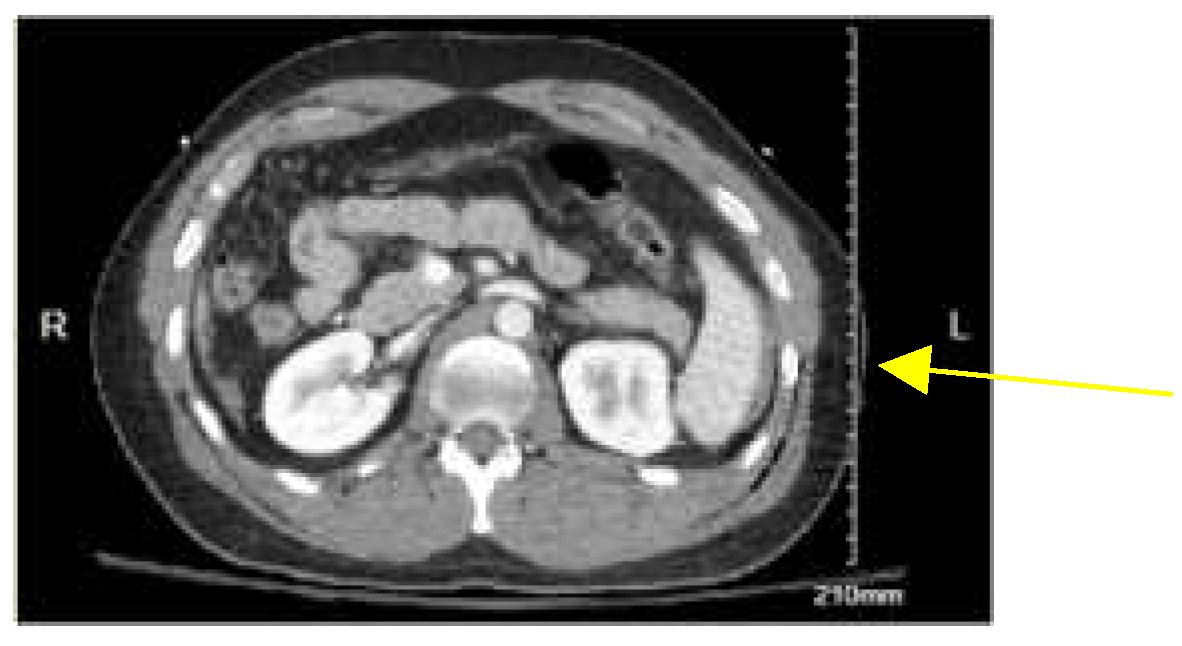

A 30-year-old non-Hispanic male with no past medical history was brought to the emergency department (ED) by the emergency medical services (EMS) after being involved in a motor vehicle accident. The patient was riding his motorcycle when he got struck on his left side by a car traveling at 30 miles per hour (mph). Per the patient, he had a helmet on which remained intact after the collision. Denies losing consciousness but was not ambulating at the scene. The patient was hemodynamically stable at the time of presentation with a BP of 110/77 mmHg. The primary survey was remarkable for mild crepitus on the left lateral chest, a major deep laceration on the left chin, a deep wound on the right knee, and an abrasion to the left flank. Extended Focused Assessment with Sonography in Trauma (eFAST) was negative for any pericardial fluid. CXR showed a rib fracture on the left without pneumothorax. CT chest revealed mildly displaced fractures of the left sixth through 12th ribs posteriorly, contusion along the left lateral chest wall, and subcutaneous emphysema. CT abdomen and pelvis (CTAP) showed grade 2 or 3 splenic laceration with a small amount of perisplenic (Figure 2) fluid for which the patient underwent embolization of the splenic artery. Due to CT chest findings of traumatic fractures of left 6th -12th ribs, the patient was taken to the operating room for left Video-Assisted Thoracic Surgery (VATS), left thoracotomy, and plating of left 7th-10th ribs. During thoracotomy exploration, it was discovered that the 10th rib had torn the diaphragm, and this was repaired with 0-ethibond running stitch and a 28French chest tube was placed on the left. The patient was discharged on postoperative day 4 with pain medication and in stable condition. ISS was 22.

Figure 2. Computed tomography (CT) with contrast showing grade 2 and 3 splenic injury with fluid around the spleen (yellow arrow).